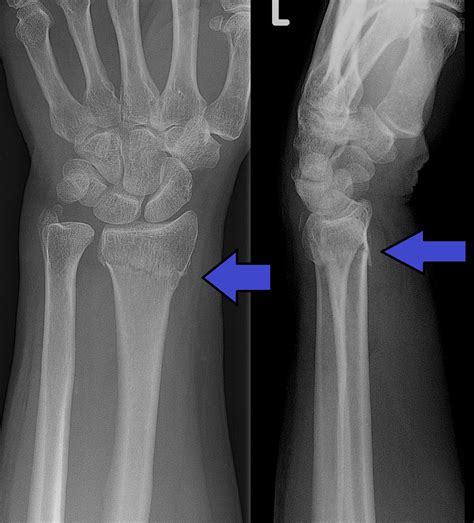

Diagnostic Procedures

Upon arriving at a medical facility, the physician will perform a physical examination followed by diagnostic imaging to confirm the Fracture Goyrand Smith. Radiographic imaging, specifically X-rays taken from multiple angles (anteroposterior and lateral views), is the gold standard for diagnosis. These images allow the doctor to determine:

Diagnostic Factor Purpose

Severity of Displacement To decide if manipulation is needed to realign the bones.

Articular Involvement To check if the fracture extends into the wrist joint surface.

Comminution To see if the bone has shattered into multiple fragments.

Nerve Involvement To rule out carpal tunnel syndrome caused by swelling.